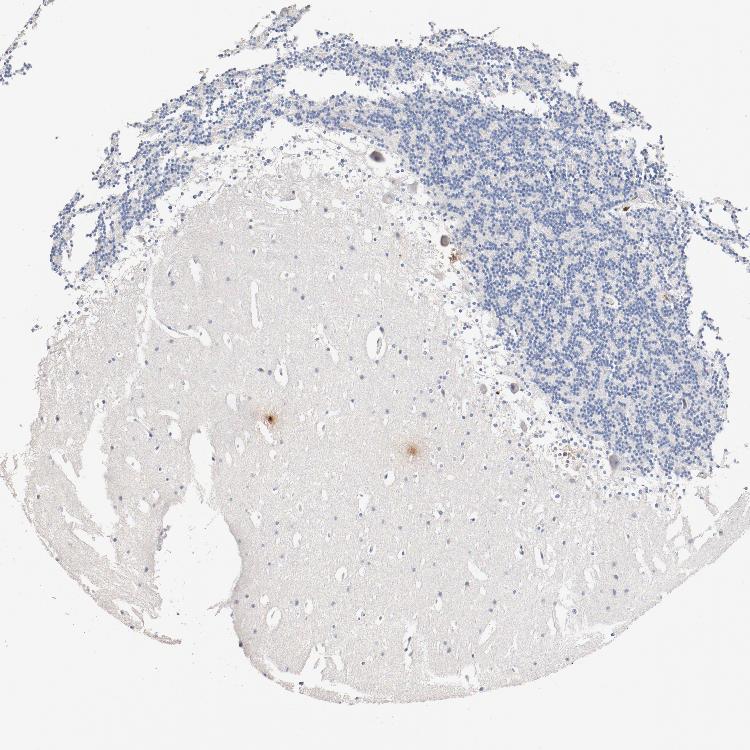

CEREBELLUM - Antibody stainingi

Antibody staining in the annotated cell types in the current human tissue is reported as not detected, low, medium, or high, based on conventional immunohistochemistry profiling in selected tissues. This score is based on the combination of the staining intensity and fraction of stained cells.

Each image is clickable and will lead to virtual microscopy that enables deeper exploration of all samples and also displays staining intensity scores, fraction scores and subcellular localization as well as patient and tissue information for each sample.

Antibody HPA008750Antibody CAB004651

Purkinje cells Not detectedNot detected

Cells in granular layer Not detectedNot detected

Cells in molecular layer Not detectedNot detected